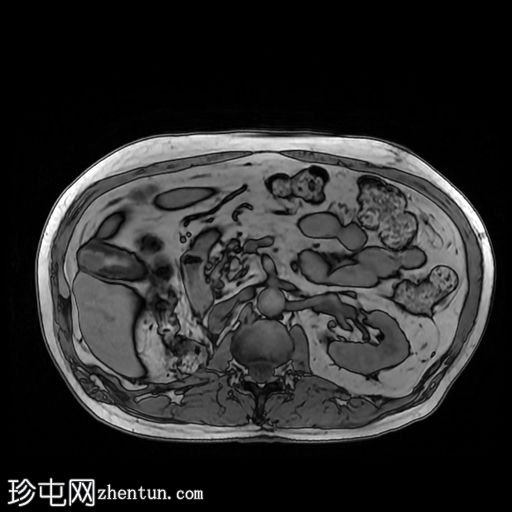

轴位增强扫描(C+)门静脉期

行CT检查以进行分期。已知肾细胞癌。已行右侧根治性肾切除术和左侧肾上腺切除术。胆囊内可见强化物质,提示胆囊底部血管受累。骨窗下胆囊内未见钙化灶。影像表现提示胆囊转移。